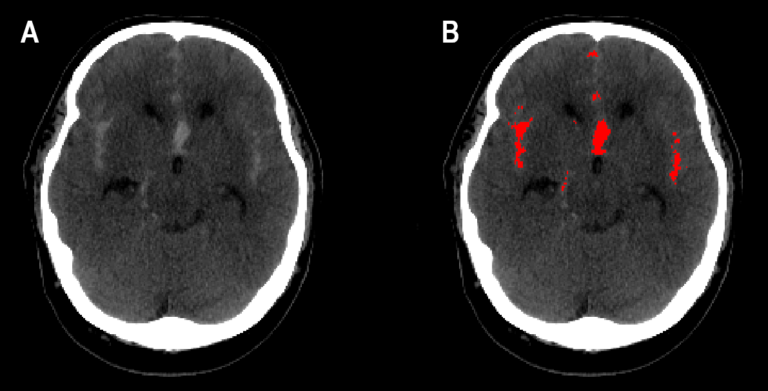

Tekoälyalgoritmi tunnistaa kuvista aivoverenvuodon

Tekoälyä opetettiin HUSissa hoidossa olleiden potilaiden pään tietokonetomografiakuvien aineistoon pohjautuen.